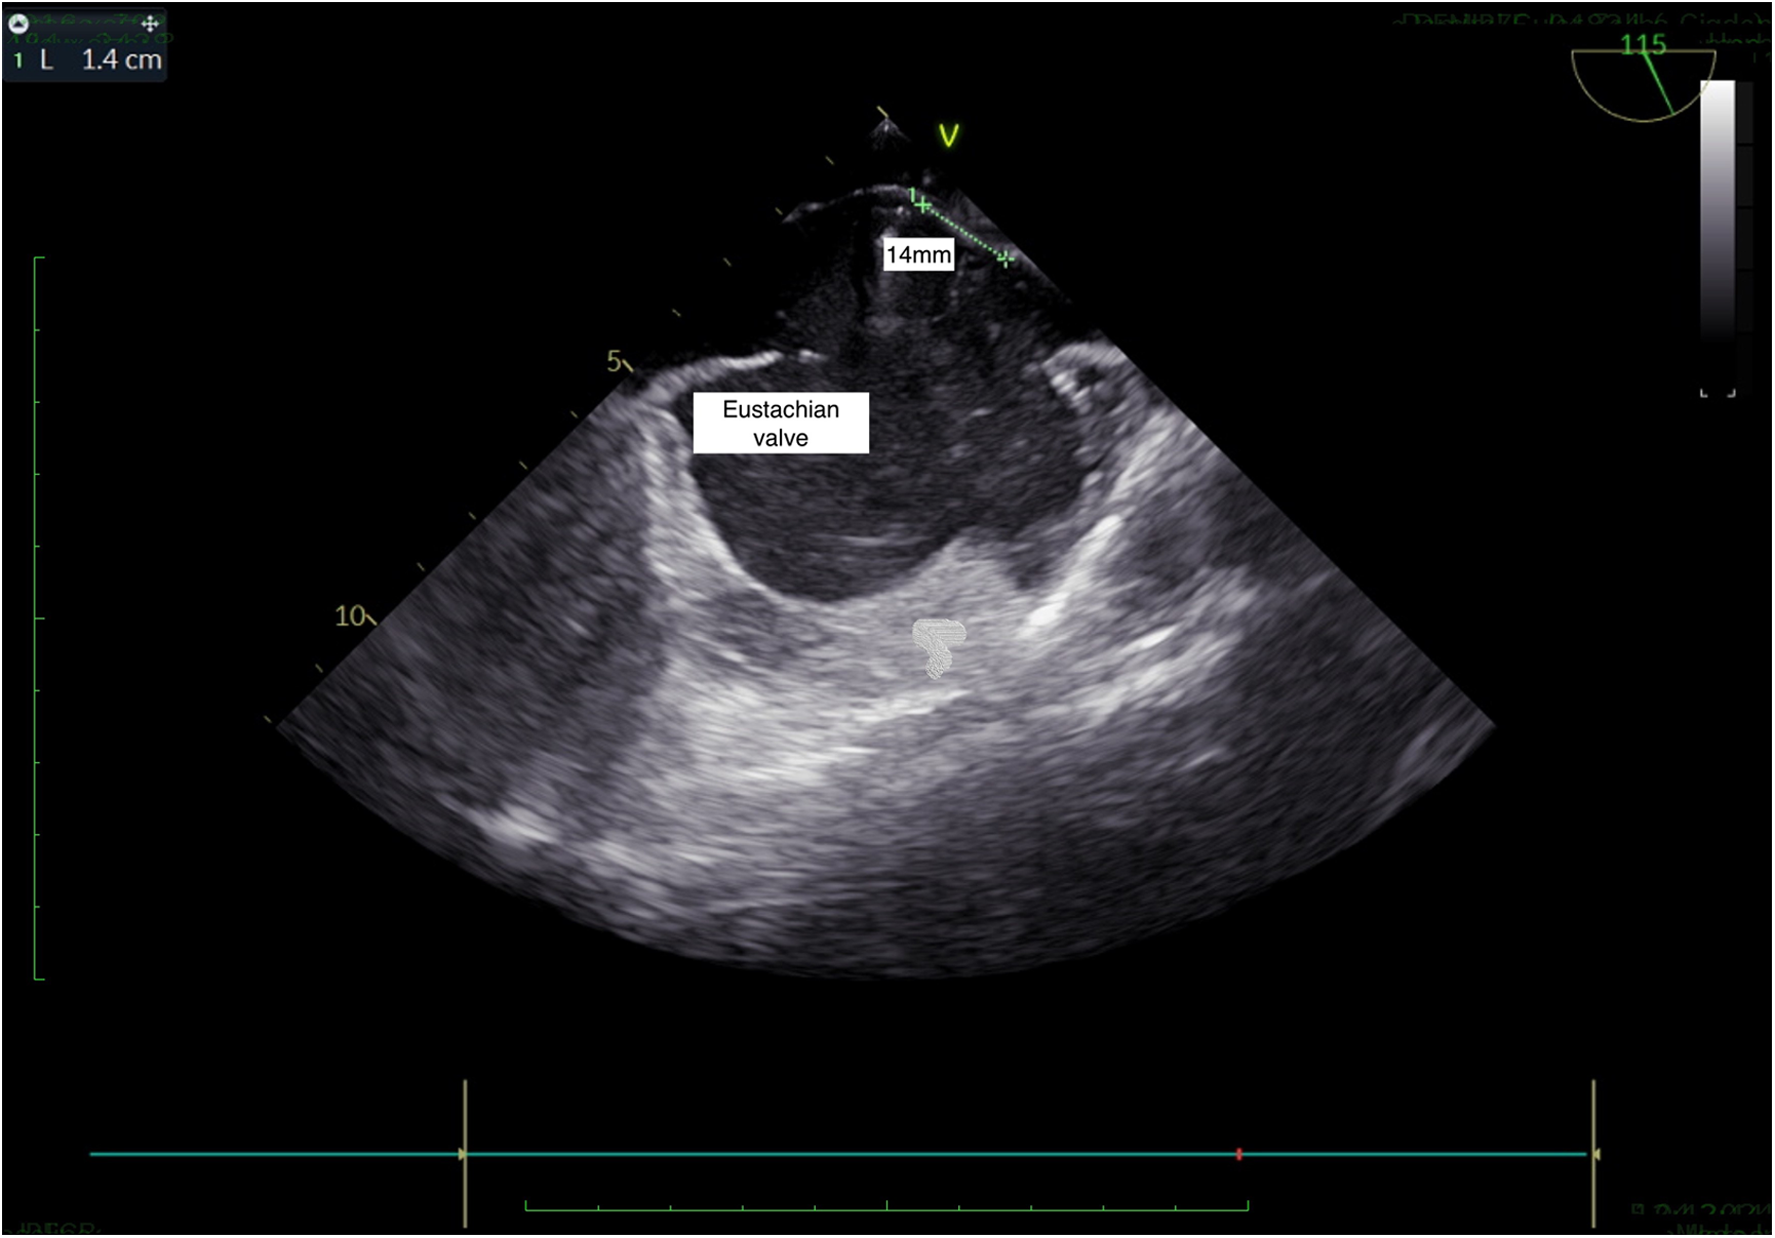

Figure 4

TEE, bicaval view: presence of Eustachian valve and PFO.

All of the patients had a >10 mm long-tunnel PFO. A floppy interatrial septum (highly mobile) was detected in 62 cases (43%). A prominent Eustachian valve was present in 47 cases (33%).

Currently, there are two main techniques described for PFO closure, namely, the tunnel technique (standard) and the transseptal technique (3). The standard technique is the most common technique for PFO closure. However, it has many disadvantages in patients with a long-tunnel PFO due to the possibility of asymmetrical device placement. The device displacement may cause a residual right-to-left shunt, thrombus formation, and incomplete endothelialization at follow-up. In the transseptal technique, the septum primum is punctured to create a new hole and the device is passed through this artificial defect (4). The controlled iatrogenic defect can form a small fenestration close to the opening of the PFO tunnel. When the closure device is deployed within this fenestration to cover the PFO tunnel, a complete closure is expected. The transseptal technique has been specifically proposed for patients with a long-tunnel PFO (4–6). Moreover, the transseptal technique has also been used in complex PFOs including those with a substantial Eustachian ridge or an overly redundant Chiari network (11).